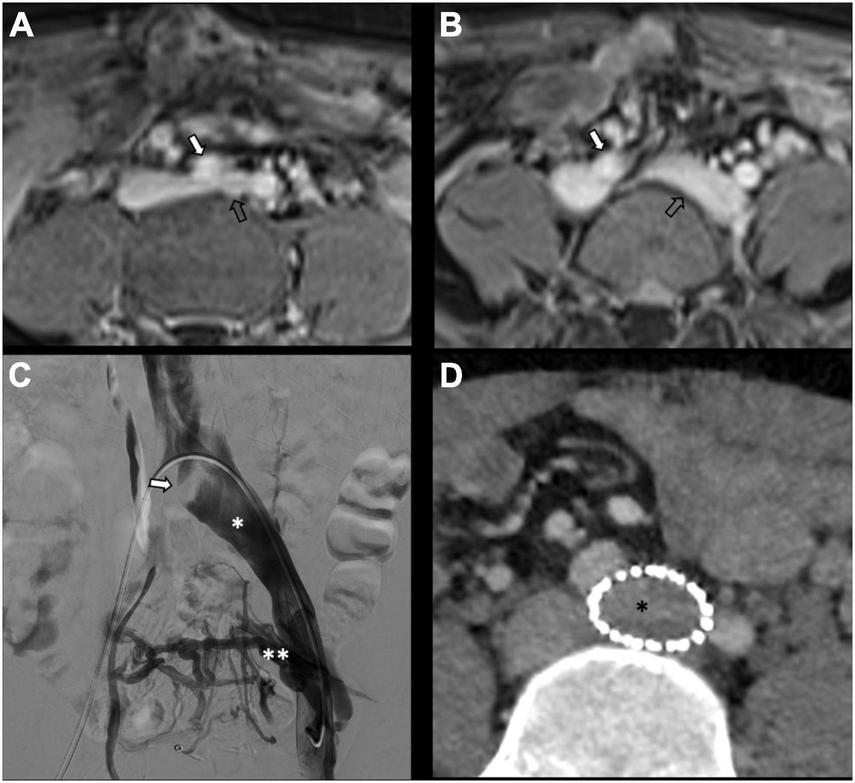

There is no consensus on how to report results, and the final results are very heterogeneous. Though, few studies, systematic reviews, and randomized trials have displayed no remarkable differences between embolization materials in terms of outcome (16, 79, 86). Furthermore, studies have reported an overall rate of complete, excellent, or moderate improvement of 75% at 4–8 weeks and more than 80% at an average of 45 months post-procedure, regardless of the technique or agent used (16, 87–90). Figure 2 shows an example of type Ia pelvic varices and subsequent vaso-occlusive therapy by means of multiple endovenous coils. Endovascular vaso-occlusive therapy is also applicable in the nutcracker phenomenon, with reported improvement in 56 to 98% of patients (17). Figure 3 shows an example of nutcracker phenomenon corresponding to a IIb pelvic varix stage. In the case of arteriovenous fistula (type IV pelvic varices), distal embolic efficacy can be achieved with liquid agents, as shown in Figure 4.

FIGURE 4

Type IV pelvic varices in a 44 yo female due to arteriovenous fistula. (A) Magnetic resonance imaging (MRI) shows right-sided pelvic varices (double white asterisks) with flow voids and early opacification in arterial phase. (B–D) Conventional phlebography shows early arterial opacification of varices (double white asterix) due to a fistula from the left internal iliac artery (white arrow), treated with Onyx embolization (single black asterisk).